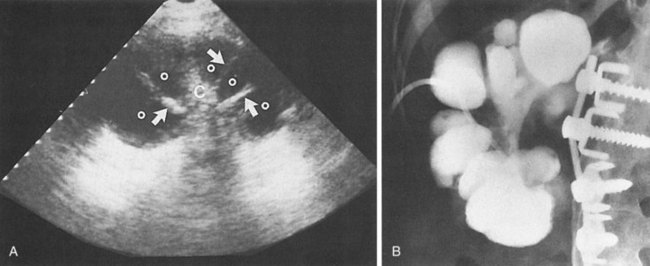

These studies are commonly used to evaluate patients initially for complicated UTIs or factors or to reevaluate patients who do not respond after 72 hours of therapy (see later). Ultrasonography (Fig. 10–19) and CT show renal enlargement, hypoechoic or attenuated parenchyma, and a compressed collecting system. They also may delineate focal bacterial nephritis and obstruction. When parenchymal destruction becomes pronounced, a more disorganized parenchyma and abscess formation associated with complicated renal and perirenal infections may be identified (Soulen et al, 1989).

Figure 10–19 Acute pyelonephritis. Ultrasound image of the right kidney demonstrates renal enlargement, hypoechoic parenchyma, and compressed central collecting complex (arrows).

(From Schaeffer AJ. Urinary tract infections. In: Gillenwater JY et al, editors. Adult and pediatric urology. Philadelphia: Lippincott William & Wilkins; 2002. p. 211–72.)

Ultrasonography and CT establish the diagnosis. On ultrasonography the lesion is typically poorly marginated and relatively sonolucent with occasional low-amplitude echoes that disrupt the cortical medullary junction (Corriere and Sandler, 1982) (Fig. 10–21A). Enhancement with a contrast agent is necessary with CT studies because the lesion is difficult to visualize on the unenhanced study (see Fig. 10–21B). Wedge-shaped areas of decreased enhancement are seen. No definite wall is evident, and frank liquefaction is absent. Conversely, abscesses tend to have liquid centers, are usually round, and are present both before and after contrast medium enhancement. More chronic abscesses may also show a ring-shaped area of increased enhancement surrounding the lesion (Corriere and Sandler, 1982). Gallium scanning reveals uptake that is in the region of and larger than the previously demonstrated mass (Rosenfield et al, 1979). In patients with multifocal disease the findings are similar but multiple lobes are involved.

Figure 10–21 Acute focal bacterial nephritis. A, Ultrasound image: longitudinal view of the left kidney demonstrates spleen (S) and left kidney (arrows). Note irregular midpole mass (M) of slightly higher echo texture than surrounding normal renal parenchyma. B, Contrast medium–enhanced CT scan demonstrates a wedge-shaped area of low density (arrows) in the middle portion of the left kidney. The findings resolved after antimicrobial therapy.

(From Schaeffer AJ. Urinary tract infections. In: Gillenwater JY et al, editors. Adult and pediatric urology. Philadelphia: Lippincott Williams & Wilkins; 2002. p. 211–72.)